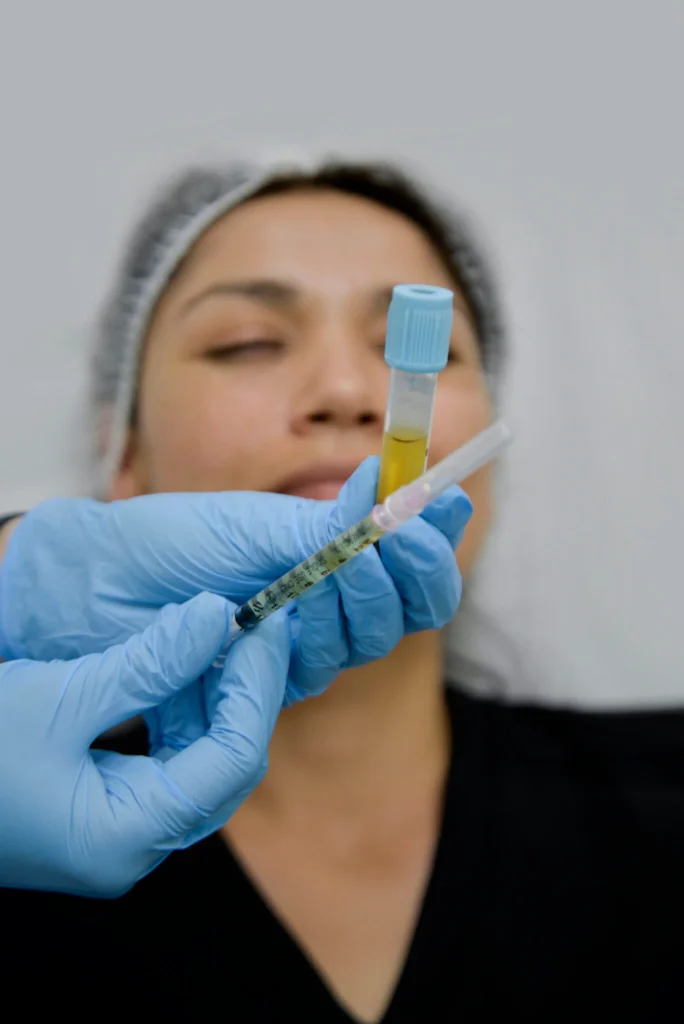

El tratamiento de Plasma Rico en Plaquetas (PRP) facial implica la inyección de plasma del propio paciente, que es rico en plaquetas y factores de crecimiento, para estimular la regeneración celular y la producción de colágeno.

Ideal para rejuvenecer la piel, mejorar la apariencia de cicatrices y promover una piel más sana y vibrante.

Los resultados pueden durar hasta un año, dependiendo del cuidado individual de la piel y factores genéticos.

El tratamiento PRP capilar utiliza inyecciones de plasma rico en plaquetas del propio paciente para revitalizar el cuero cabelludo y estimular el crecimiento del cabello.

Recomendado para tratar la caída del cabello y mejorar la densidad capilar.

Los efectos se ven progresivamente y pueden requerir sesiones de mantenimiento cada 6 a 12 meses.